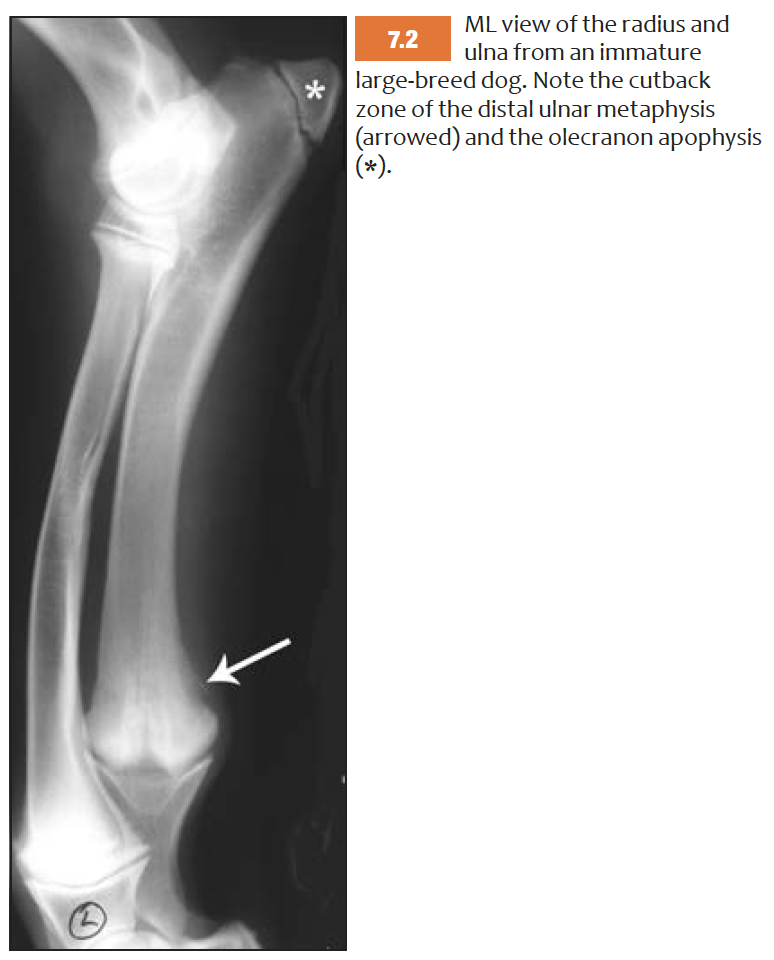

What are apophyses?

Non-articular cartilagenous protuberances -> ossify.

In young animal seperated from body of bone by cartilageneous band which fuse when mature

Sites of tendious attachement

What is the cutback zone?